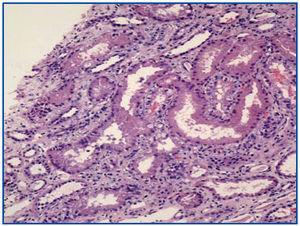

Se realizó biopsia renal en la se mostraban 9 glomérulos, 5 de ellos completamente esclerosados y 4 presentaban lesiones de esclerosis segmentaria; en estos últimos, destacaba una hiperplasia e hipertrofia del epitelio visceral (pseudosemilunas) (Figura 1), en ocasiones, vacuolizado (PAS +), ocupando el espacio de Bowman pero con epitelio parietal no afecto. Los capilares de estos glomérulos presentaban áreas de colapso y oclusión luminal (Figura 2). El intersticio era edematoso, con moderada infiltración inflamatoria mixta y túbulos muy alterados, con dilatación de luces y epitelio, a veces, necrótico o degenerado y células desprendidas en su luz (Figura 3). El componente vascular no mostraba lesiones.

Figura 2. Colapso de capilares glomerulares. Meteramina Plata 40x. El estudio de estudio de autoinmunidad, que incluía ANA, ANCA y anti-ADN, fue negativo. En el estudio ecográfico renal se observaron unos riñones simétricos, de tamaño normal (riñón derecho 11,5 cm,